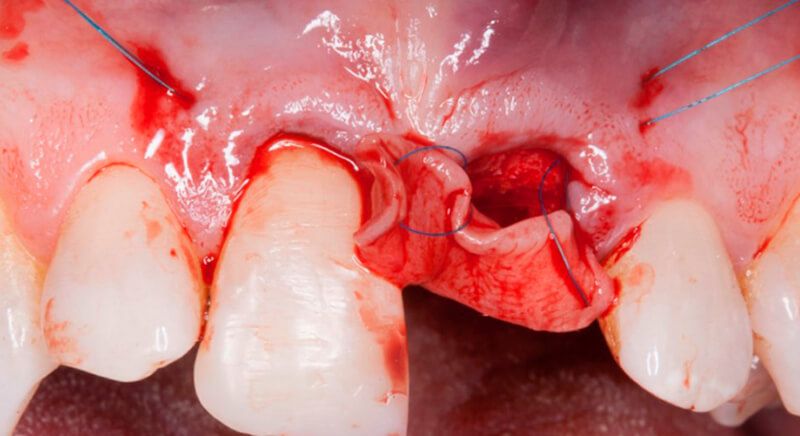

Once tooth 2.1 had been extracted, it was decided that it was not advisable to place an implant immediately as the bone conditions were not ideal and the gum did not have sufficient thickness. We opted for a treatment to preserve the socket and to delay implant insertion.

The socket was filled with a xenograft after the extraction and a graft of connective tissue was placed in the vestibular area of the two upper central incisors.

The tissue with epithelium was taken from the palate and de-epithelialized outside of the mouth. This obtains a lamina propria graft with better density and quality than if it were obtained with a single incision to the palate.